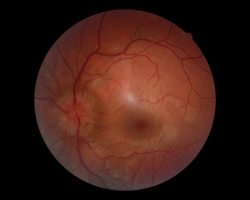

- Rétinophotographies des deux yeux : œdème papillaire bilatéral majeur en faveur HTIC

FO : cf. images jointes